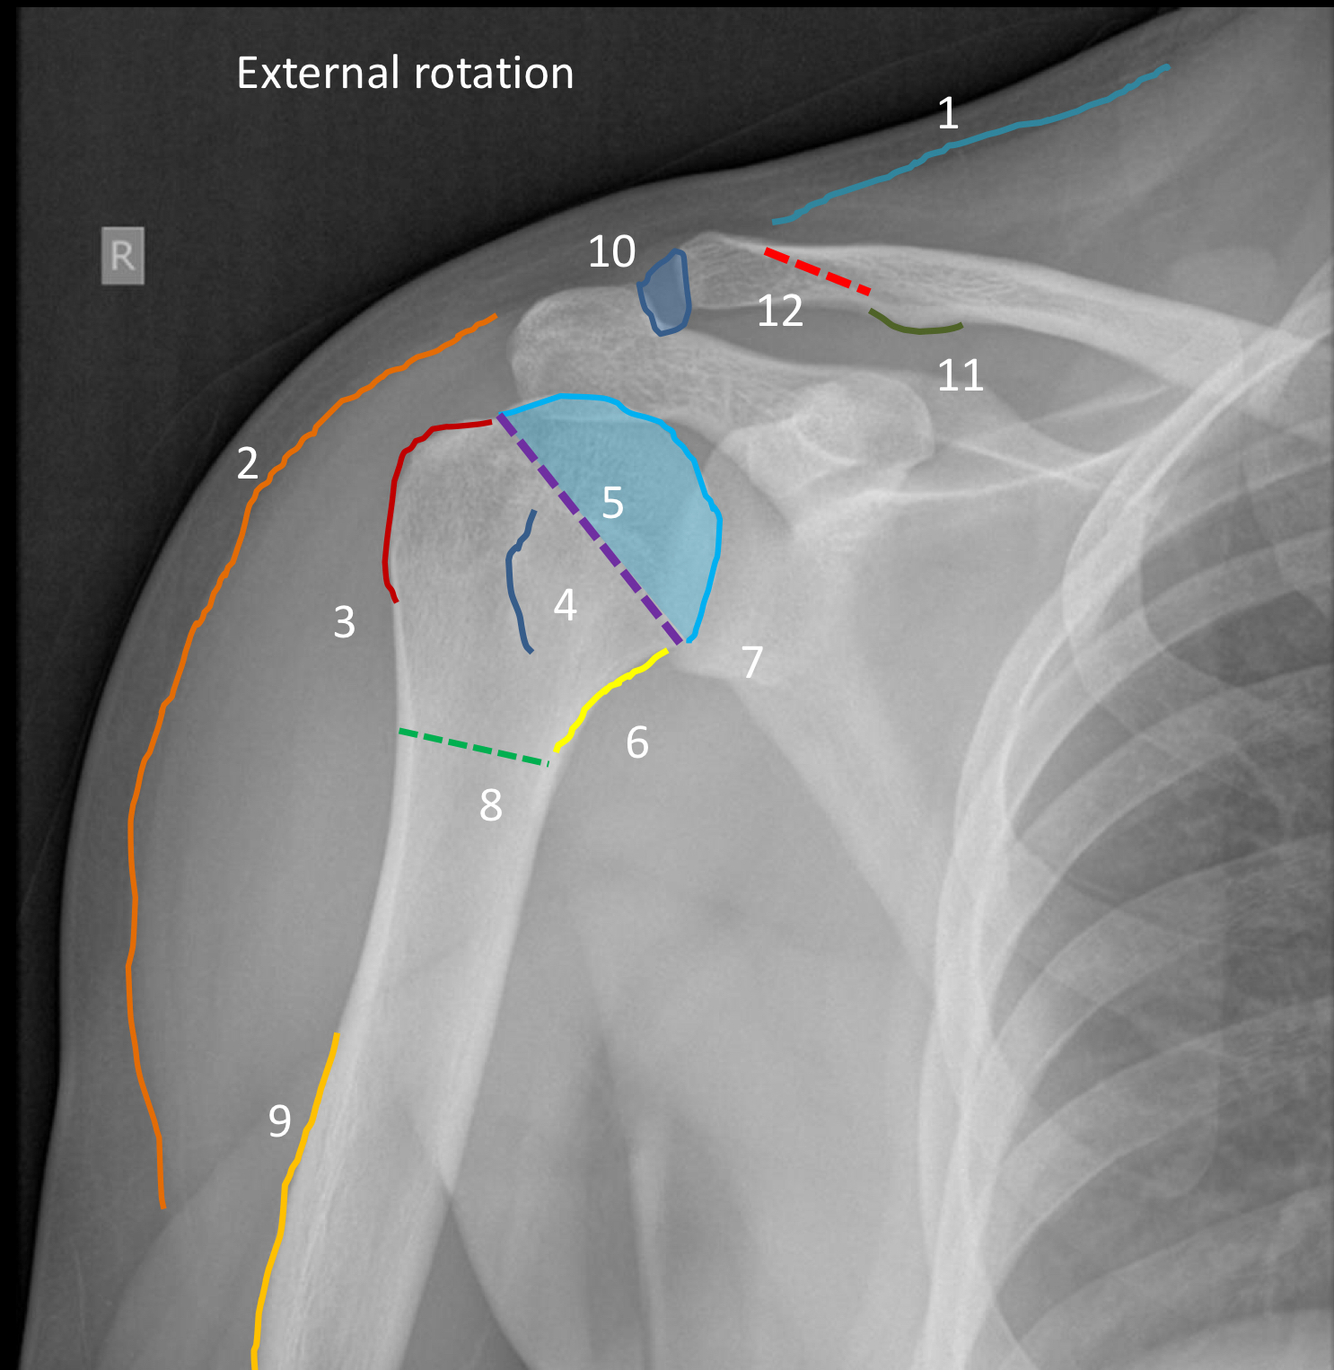

What view is this?

AP shoulder with external rotation

What is the Blue arrow point to?

greater tuberosity of the humerus (which will be more lateral in external rotation)

What is the red area outlining?

lesser tuberosity of the humerus (will be superimposed on metaphysis with external rotation)

1?

superior margin of trapezius muscle

2?

lateral margin of deltoid muscle

3?

greater tuberosity of the humerus

4?

lesser tuberosity of the humerus

5?

humeral head

6?

medial margin of humeral metaphysis

7 (dotted purple line)?

anatomical neck of humerus

8 (green dotted line)?

surgical neck humerus

9?

deltoid tuberosity

10?

acromioclavicular joint space

11 (dark green line)?

conoid tubercle

12?

trapezoid line or ridge of clavicle